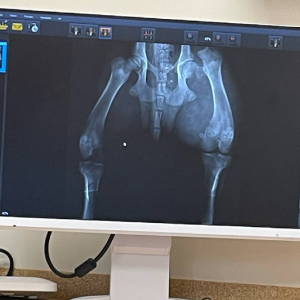

Z przykrością informujemy, że mimo naszych starań i konsultacji z lekarzami weterynarii, musieliśmy podjąć bardzo trudną decyzję o eutanazji pieska. Tomografia komputerowa wykazała znacznie więcej urazów, niż wcześniej przypuszczano – w tym liczne złamania oraz oderwanie miednicy.

Dolar to wierny towarzysz codzienności, który niespodziewanie znalazł się w dramatycznej sytuacji. W wyniku wypadku doszło do poważnego złamania. Opiekunka natychmiast pojechała z Dolarem do najbliższego lekarza weterynarii, gdzie zostało wykonane zdjęcie RTG. Stopień oraz skomplikowanie złamania są na tyle duże, że Dolar musi być leczony w klinice specjalizującej się w tego typu operacjach.

„Mamy do czynienia ze złuszczeniem głowy kości udowej i być może jeszcze z złuszczeniem krętarza większego kości udowej. Możemy podjąć się leczenia natomiast złamanie to wymaga wykonania dodatkowych RTG lub TK.”